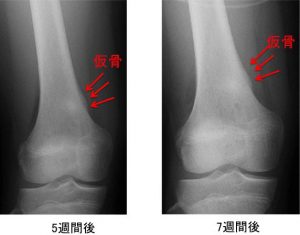

これらの検査は、腫れや痛みの根本的な原因を特定するのに役立ちます。タマネギの皮の骨膜反応は、複数の層の骨のように見えます。

タマネギの皮膚の骨膜反応は、ユーイング肉腫などの疾患の存在を示している可能性があります。良性腫瘍の結果である可能性もあります。

画像検査だけでは医師が症状の重症度を判断することはできません。代わりに、一部の専門家は、重症度を判断する 1 つの方法として、成長の速度を調べることを提案しています。その後、それらを遅い成長と速い成長に分類できます。